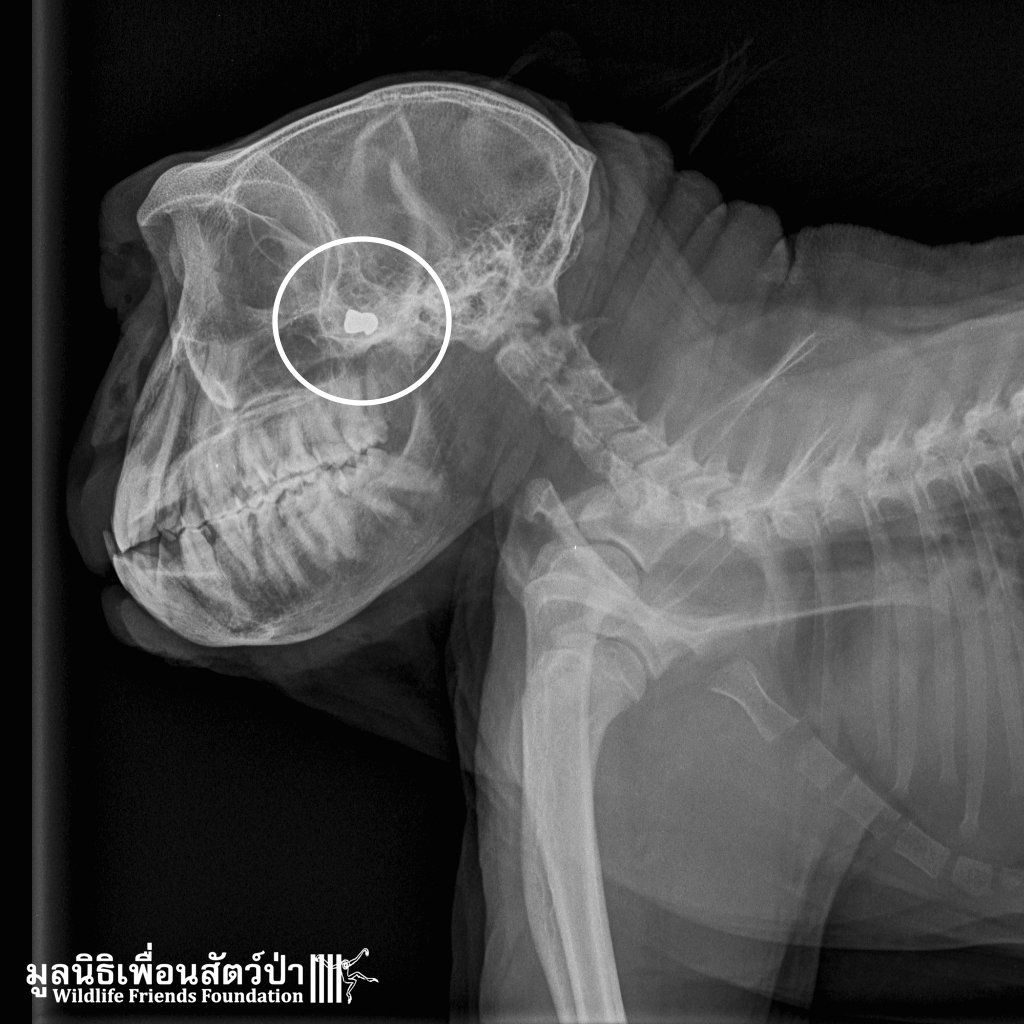

After 2 and a half weeks of intensive care at the WFFT Wildlife Hospital ‘Frank’ the macaque that got shot in the face has been released back to a safe protected area. Stay out of trouble please Frank. See his rescue story at https://www.wfft.org/primates/rescued-macaque-shot-in-the-face/